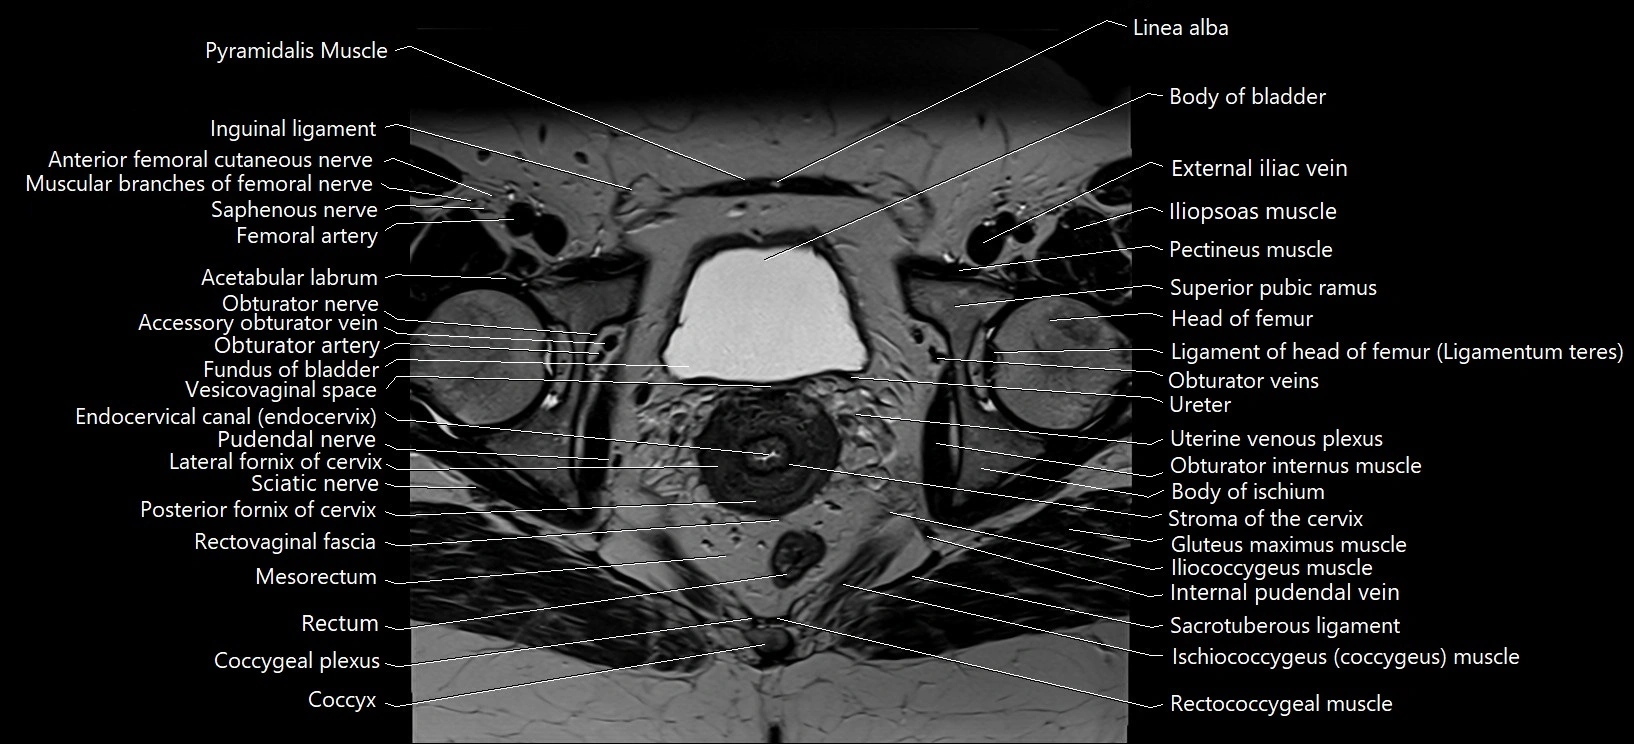

- Accessory obturator artery

- Accessory obturator vein

- Acetabular labrum

- Body of ischium

- Body of urinary bladder

- Co (Coccyx)

- Coccygeal plexus

- Coccyx

- Endocervical canal

- External iliac vein

- Fundus of urinary bladder

- Head of femur

- Iliococcygeus muscle

- Iliopsoas muscle

- Internal pudendal vein

- Lateral fornix of cervix

- Ligamentum teres (ligament of the head of femur)

- Linea alba

- Mesorectum

- Obturator artery

- Obturator externus muscle

- Obturator internus muscle

- Obturator nerve

- Obturator veins

- Posterior fornix of cervix

- Pudendal nerve

- Rectococcygeal muscle

- Rectum

- Sacrotuberous ligament

- Sciatic nerve

- Stroma of the cervix

- Superior pubic ramus

- Uterine venous plexus

- Vesicovaginal space